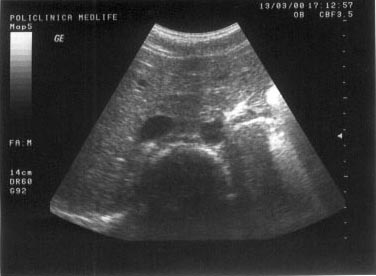

Figura 20. Delimitare neta intre ficat si rinichi. |

Figura 21. Scleroza renala - rinichiul drept prezinta contur neregulat si este imprecis delimitat. |